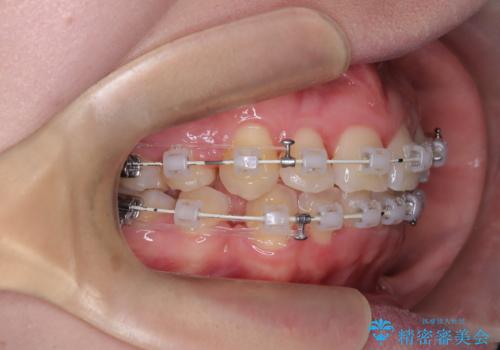

- 審美ワイヤー装置

- 患者様は、結婚式までに歯並びを整えたいとのご要望で来院されました。診断の結果、上下左右の第一小臼歯を抜歯し、歯列全体を整える計画としました。審美性を重視し、目立ちにくいホワイトワイヤーを使用した矯正を提案しました。治療期間は2年を目安とし、結婚式までに前歯の整列と噛み合わせを優先的に整えるスケジュールで進めました。定期的な調整と経過観察を通じて、計画的に治療を進めました。

結婚式までに仕上げるため、通常よりも細かく調整を行い、歯の動きを効率的に管理しました。審美ワイヤーを使用したことで、治療中も目立ちにくく、写真撮影などの日常生活での見た目の負担を軽減しました。抜歯部分のスペースを閉じる際には、前歯の位置や噛み合わせのバランスに配慮し、過度な力がかからないよう進めました。患者様の大切なイベントに間に合うよう治療計画を立て、理想的な仕上がりを実現しました。